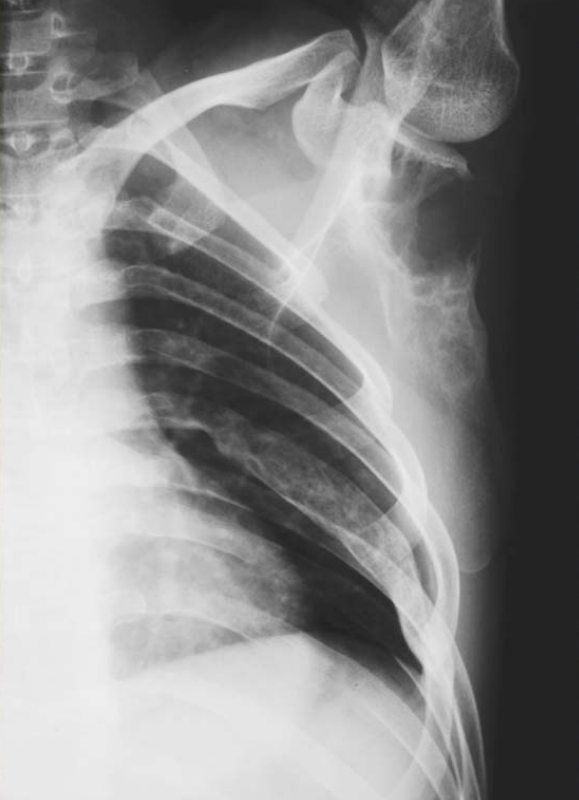

Figure2